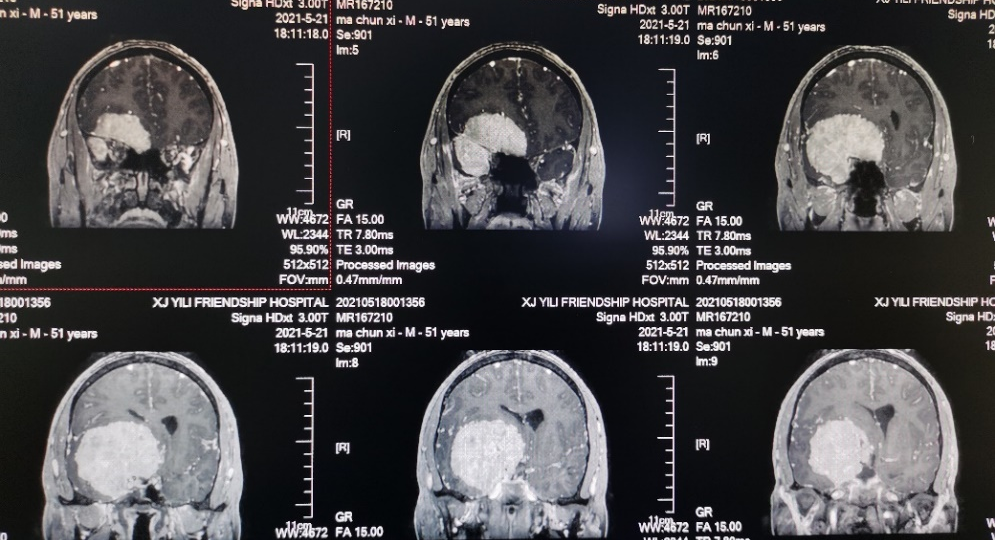

病例介绍

01

02

03

04